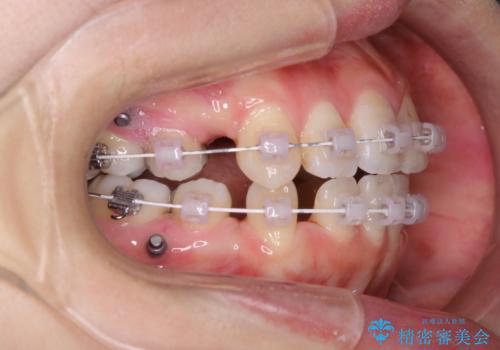

- ワイヤー矯正中のメンテナンスでPMTCを希望されました。染め出しを行い、歯ブラシ指導とPMTC30分コースを行いました。

毎日しっかりと磨いているようでも、装置の周りや歯と歯の間・歯と歯茎の間に磨き残しが残ってしまいます。そのため磨き残しをチェックする『染め出し剤』を使用すると明確に磨き残しを見ることができます。

染め出されている部分の磨き残しは、毎日の習慣として歯ブラシをしていてもいつも磨けてない部分です。